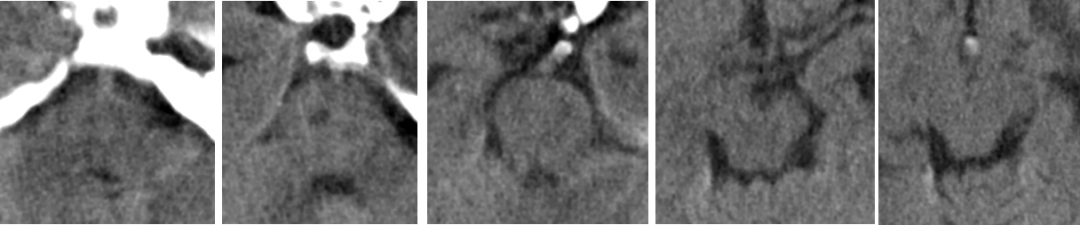

2014-11-18 0am CT

2014-11-18 10am CT